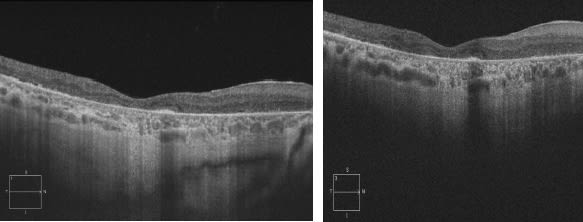

Sub-RPE imaging is specifically useful in the management of suspected choroidal disorders, such as central serous chorioretinopathy, AMD, choroidal tumors and retinitis pigmentosa (Figures 1 and 2).4

Figure 2. Even when the choroid was fully visible at 840 nm (left), considerable additional detail was visible at 1,050 nm (right).